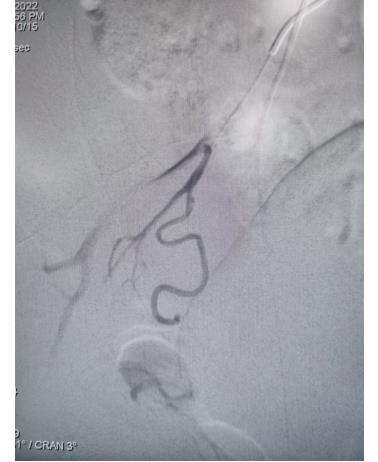

冠脈手術前